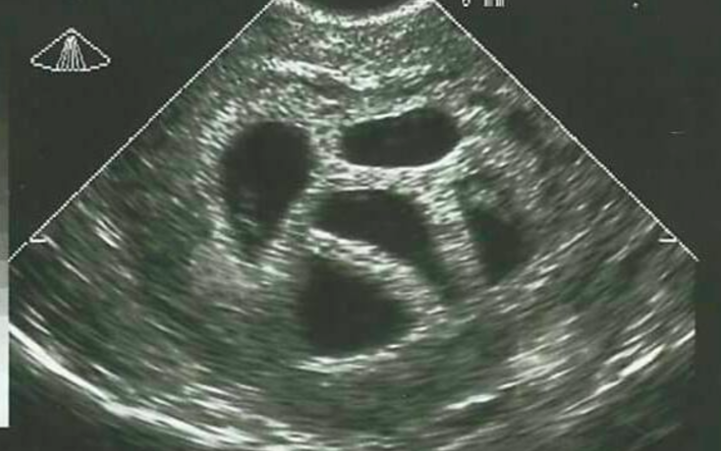

Selective reduction

Selective reduction means that one or more embryos or foetuses are killed and/or removed to increase the chances of survival for the other(s). When Susan refused to do this, the doctor sent her to a specialist, who also tried to convince her to continue her pregnancy with only a selection of the embryos. Nevertheless, Susan and her husband stuck with their decision. It was the best decision they could have made!